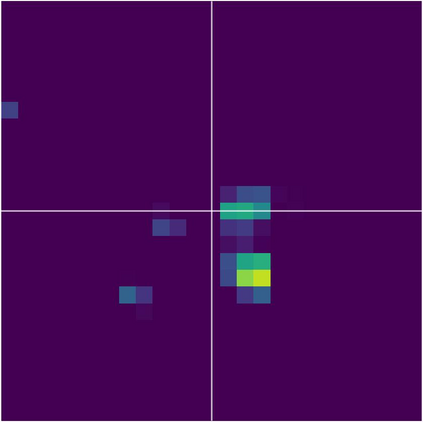

Various imaging modalities allow for time-dependent image reconstructions from measurements where its acquisition also has a time-dependent nature. Magnetic particle imaging (MPI) falls into this class of imaging modalities and it thus also provides a dynamic inverse problem. Without proper consideration of the dynamic behavior, motion artifacts in the reconstruction become an issue. More sophisticated methods need to be developed and applied to the reconstruction of the time-dependent sequences of images. In this context, we investigate the incorporation of motion priors in terms of certain flow-parameter-dependent PDEs in the reconstruction process of time-dependent 3D images in magnetic particle imaging. The present work comprises the method development for a general 3D+time setting for time-dependent linear forward operators, analytical investigation of necessary properties in the MPI forward operator, modeling aspects in dynamic MPI, and extensive numerical experiments on 3D+time imaging including simulated data as well as measurements from a rotation phantom and in-vivo data from a mouse.